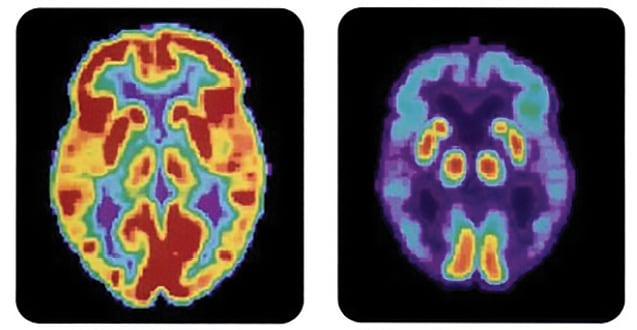

One application of radiopharmaceuticals is in positron emission tomography (PET) scan imaging. Here PET scans show the difference between a normal brain (left) and the brain of a patient with Alzheimer’s disease.